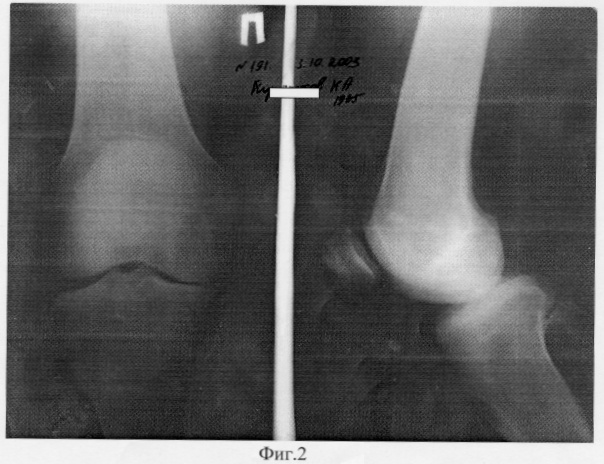

Больной К. 69 лет страдал правосторонним гонартрозом в течение 10 лет. За последний 2003 год из-за сильной боли в правом коленном суставе резко снизилась опороспособность правой нижней конечности, а функция коленного сустава резко уменьшилась (фиг.2 – состояние до операции).

28.11.2003 года выполнена операция: реконструктивно-восстановительная с транспозицией участков мыщелков правой бедренной кости. Послеоперационный период протекал без осложнений (фиг.3 – состояние после операции).